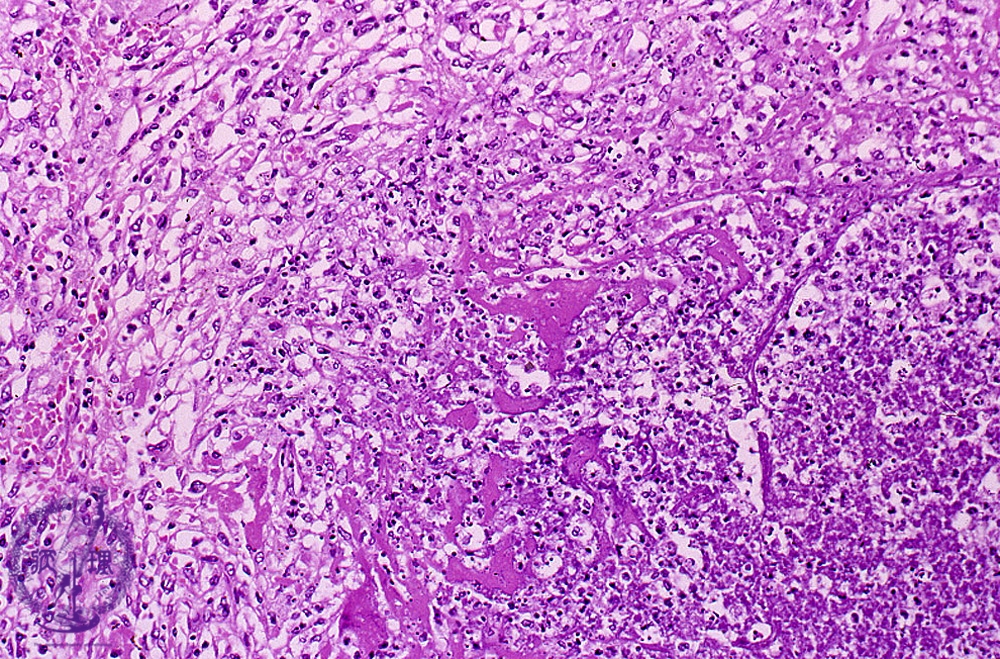

- ★(7)Bacterial pneumonia (lung abscess)

Microscopic view (HE stain, high power view): On the right, there is abscess composed of inflamed necrotic debris (dotted line) surrounded by granulation tissue (left). Granulation tissue consists of fibroblasts, inflammatory cells and capillaries.